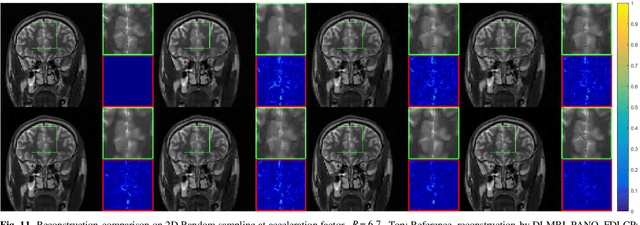

Abstract:Deep learning, particularly the generative model, has demonstrated tremendous potential to significantly speed up image reconstruction with reduced measurements recently. Rather than the existing generative models that often optimize the density priors, in this work, by taking advantage of the denoising score matching, homotopic gradients of generative density priors (HGGDP) are proposed for magnetic resonance imaging (MRI) reconstruction. More precisely, to tackle the low-dimensional manifold and low data density region issues in generative density prior, we estimate the target gradients in higher-dimensional space. We train a more powerful noise conditional score network by forming high-dimensional tensor as the network input at the training phase. More artificial noise is also injected in the embedding space. At the reconstruction stage, a homotopy method is employed to pursue the density prior, such as to boost the reconstruction performance. Experiment results imply the remarkable performance of HGGDP in terms of high reconstruction accuracy; only 10% of the k-space data can still generate images of high quality as effectively as standard MRI reconstruction with the fully sampled data.